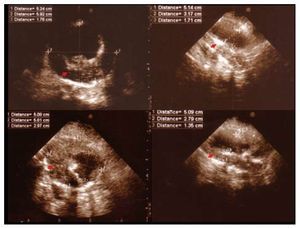

- A 72-year-old woman with cardiovascular risk factors and ischaemic heart disease. After studying the abdominal aorta during TTE (for sub-costal and paraumbilical access), a large aneurysm was seen of the entire abdominal aorta, 6.5´5.5 cm, calcified with severe circumferential mural thrombosis and effective diameter <2.6 cm in diameter (Figure 1). A CT scan confirmed the findings.

Figure 1. A: echocardiography, aneurysm of the infrarenal abdominal aorta, calcified and thrombosed (arrow). B: CT scan with contrast, cross-section. C: coronal sections. D: sagittal sections.